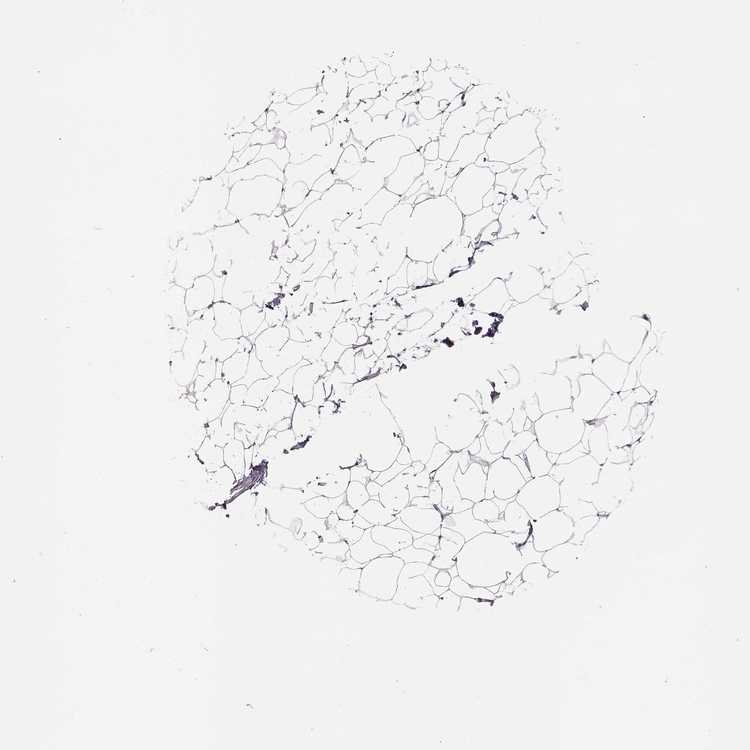

BREAST - Antibody stainingi

Antibody staining in the annotated cell types in the current human tissue is reported as not detected, low, medium, or high, based on conventional immunohistochemistry profiling in selected tissues. This score is based on the combination of the staining intensity and fraction of stained cells.

Each image is clickable and will lead to virtual microscopy that enables deeper exploration of all samples and also displays staining intensity scores, fraction scores and subcellular localization as well as patient and tissue information for each sample.

Antibody HPA072947

Adipocytes Not detected

Glandular cells Not detected

Myoepithelial cells Not detected